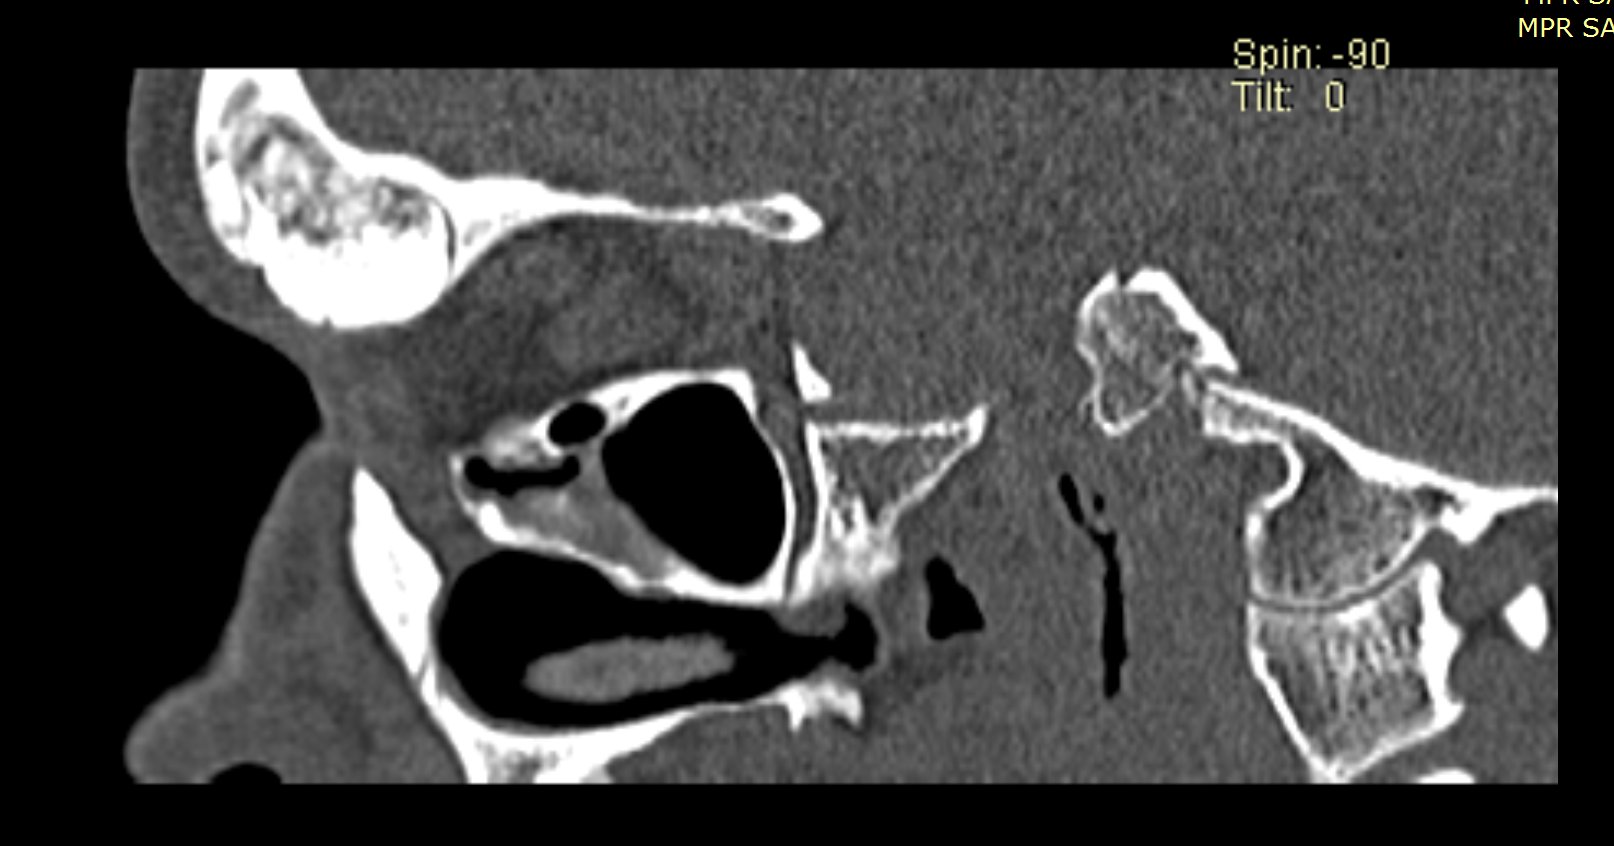

Examenul clinic ORL și examenele imagistice complementare (CT, RMN sinusuri paranazale) pun în evidență o formațiune tumorală osteogenică a sinusului frontal drept, protruzivă în unghiul supero-intern al orbitei, extinsă medial către sinusul frontal stâng.

- Se expune formațiunea tumorală osteomatoasă care ocupă în totalitate cavitatea sinusală frontală dreaptă, se extinde către sinusul frontal controlateral și către orbita dreaptă, creând presiune pe atmosfera celulo-grasoasă periorbitară la nivelul unghiului supero-intern OD. Formațiunea este intens aderentă la nivelul peretelui sinusal postero-superior. Aceasta prezintă două zone de consistență diferită.